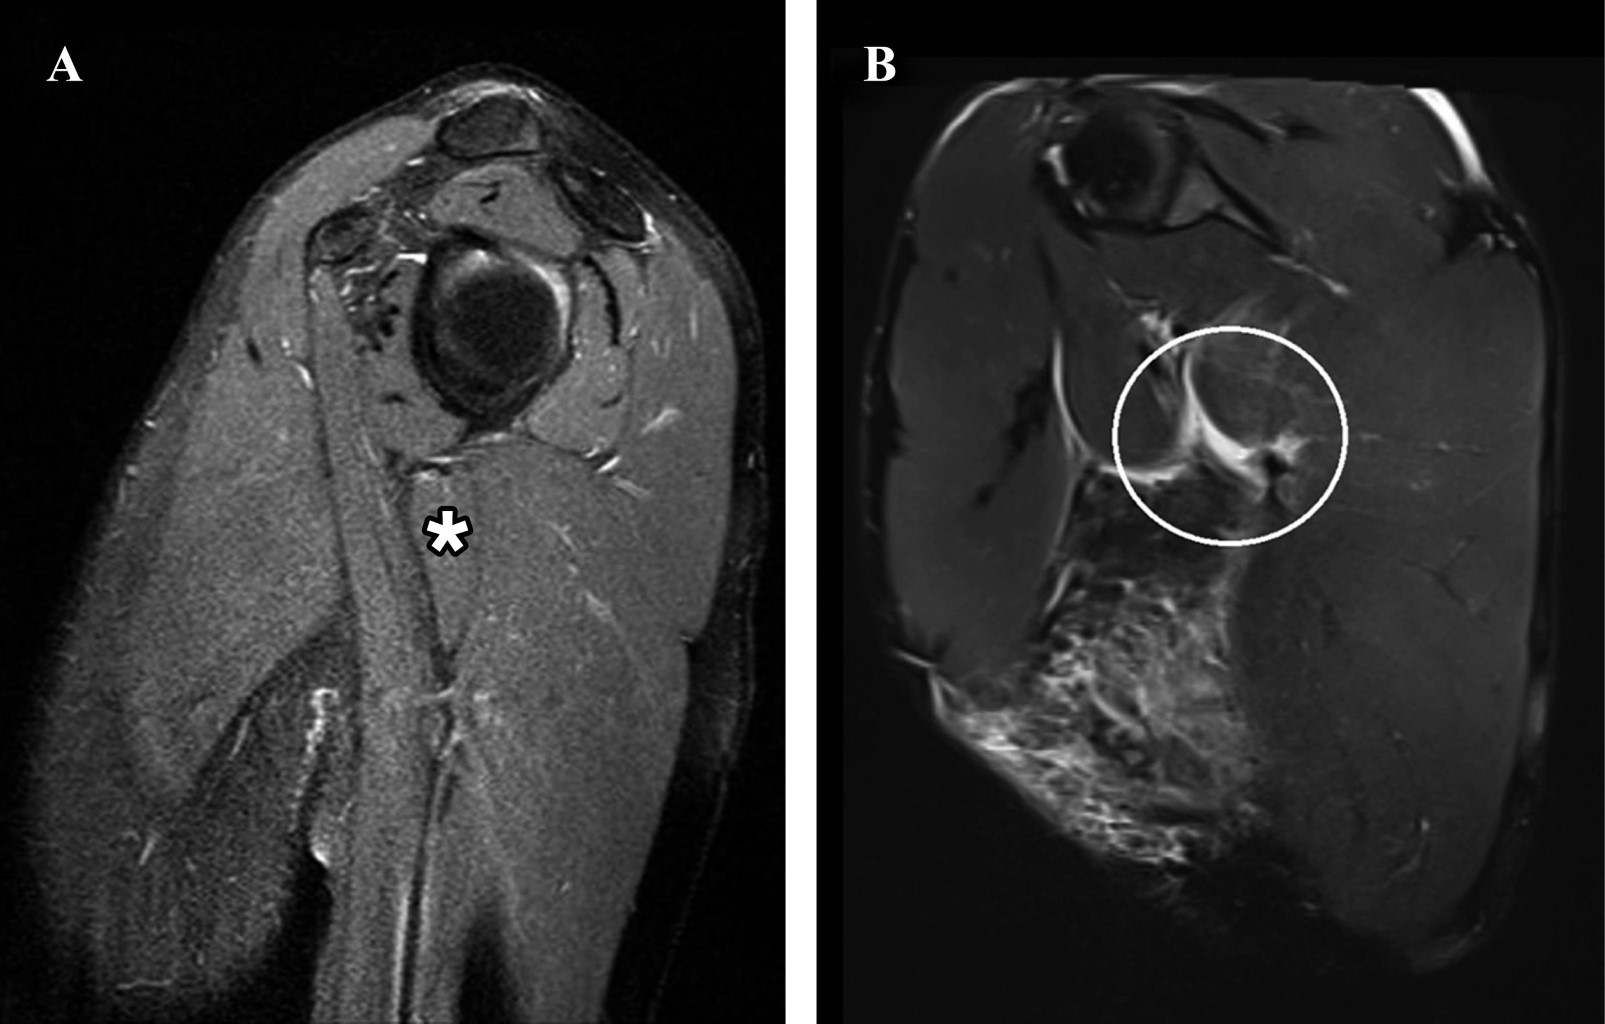

La rotura del músculo redondo mayor es una afección muy conocida en actividades deportivas como el béisbol, el hockey y el tenis. No existe un consenso real en la literatura sobre el tratamiento, y los enfoques varían entre métodos funcionales y quirúrgicos. Si bien el tratamiento funcional parece ser una opción viable, falta evidencia que indique una mejora significativa en la fuerza de rotación medial después de dicho tratamiento. Presentamos a un hombre de 30 años con dolor debajo de la axila derecha durante los últimos 10 días, atribuido al entrenamiento de jiu-jitsu, que reveló un desgarro completo de la unión musculotendinosa del redondo mayor y un desgarro de inserción parcial (aproximadamente el 75% de espesor) de los tendones supraespinoso e infraespinoso, junto con atrofia en la transición musculotendinosa del pectoral mayor. El paciente fue tratado con medicación analgésica, acompañada de tratamiento fisioterapéutico que incluyó electrotermofototerapia, terapia con láser/LED, terapia manual y un régimen de ejercicio estructurado durante 14 semanas, reintroduciendo gradualmente el entrenamiento deportivo específico.

Figura 3